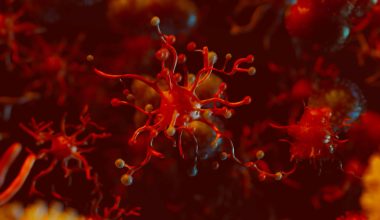

Σύμφωνα με τα στοιχεία του Παγκόσμιου Οργανισμού Υγείας, εκατομμύρια άνθρωποι εκτιμάται ότι χάνουν κάθε χρόνο τη ζωή τους λόγω καρδιαγγειακών επιπλοκών.

Παρά το γεγονός ότι τα καρδιαγγειακά νοσήματα είναι τόσο συνηθισμένα, συχνά είναι δύσκολο να αναγνωριστούν τα σχετικά προειδοποιητικά συμπτώματα.

Επιστήμονες μάλιστα αναφέρουν ότι υπάρχουν και κάποια παράδοξα σημάδια που μπορεί να φανερώνουν προβλήματα με την καρδιά.

Δείτε τρία από αυτά…

1. Κακοσμία στόματος

Σύμφωνα με μελέτη οι περιοδοντικές παθήσεις, σύμπτωμα των οποίων είναι η κακοσμία του στόματος, προωθούν την εκδήλωση φλεγμονής. Η φλεγμονή με τη σειρά της συμβάλλει στην εκδήλωση εγκεφαλικού επεισοδίου και καρδιοπάθειας.

2. Ρυτίδες στους λοβούς των αυτιών

Οι διαγώνιες πτυχώσεις στους λοβούς των αφτιών μπορεί να αποτελούν ένδειξη ότι η καρδιά δεν λειτουργεί σωστά, δείχνει μελέτη από το Πανεπιστήμιο της Πενσυλβάνια. Το σύμπτωμα συνδέεται κυρίως με απόφραξη στις αρτηρίες.

3. Ζαλάδα από την αλλαγή θέσης

Πρόκειται για ένα χαρακτηριστικό σύμπτωμα της ορθοστατικής υπότασης. Στις περισσότερες περιπτώσεις, η ενόχληση διαρκεί μερικά δευτερόλεπτα, εάν όμως επιμένει για μερικά λεπτά μπορεί να υποδεικνύει διαταραχή στην κυκλοφορία του αίματος, σύμφωνα με μελέτη. Τα άτομα που εκδηλώνουν αυτό το είδος ζαλάδας εκτιμάται ότι έχουν 54% περισσότερες πιθανότητες να εκδηλώσουν αργότερα καρδιακή ανεπάρκεια.